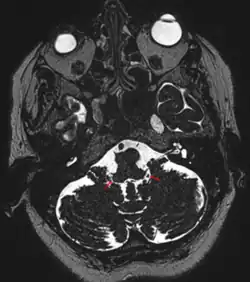

Ouvertures latérales du IVe ventricule

Les ouvertures latérales du IVe ventricule sont des ouvertures au niveau des cornes latérales du IVe ventricule[1],[2] permettant le passage du liquide cérébro-spinal. Ils étaient anciennement appelés trous ou foramina de Luschka, ou bien foramina de Retzius[3].

Leur existence physiologique est contestée, certains estimant qu'ils apparaissent uniquement en cas d'hyperpression ventriculaire[4].